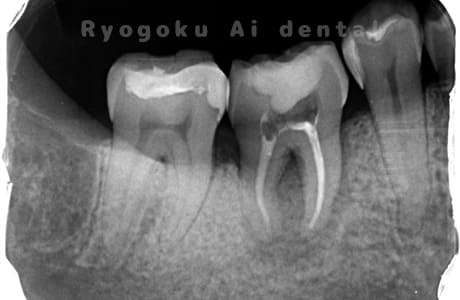

Case04

-

- 原因

- 慢性根尖性歯周炎

- 治療内容

- 自家歯牙移植

- 治療費用

- 220,000円

他院で抜歯し、インプラントを進められた患者さんです。親知らずが残っていたため、移植治療がベストと判断し、治療を行いました。

<リスク・副作用>

治療後、痛みや違和感、出血、腫れなどが出る事があります。喫煙者、糖尿病などの方の場合、歯が生着しない場合があります。